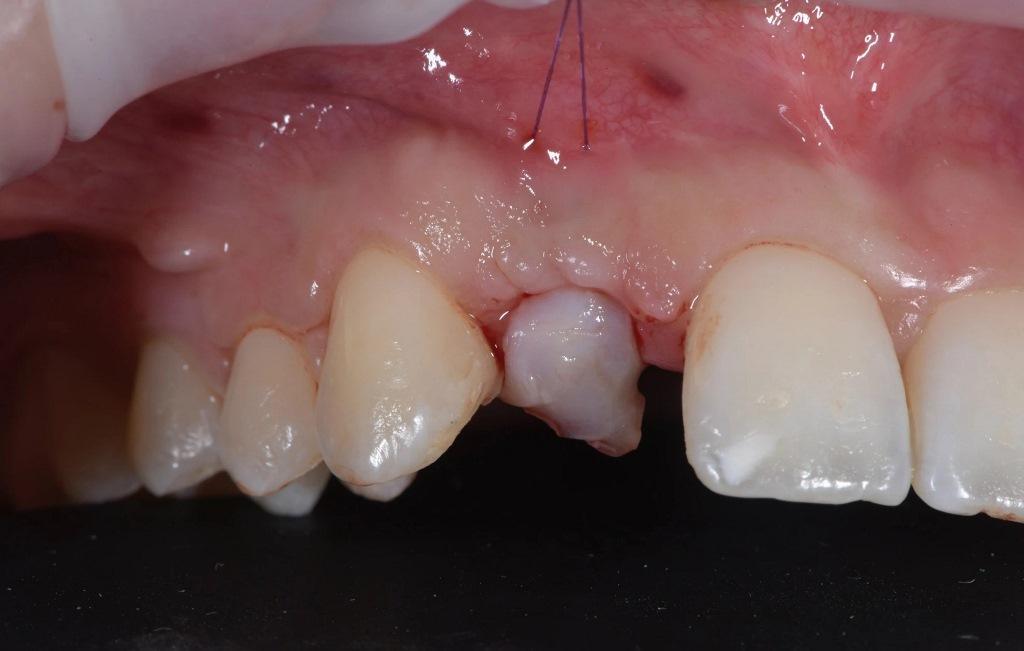

Анестезия проводилась с использованием 4%-ного раствора артикаина с добавлением адреналина в соотношении 1:100 000 (Убистезин, 3M ESPE). С помощью лезвия №15с был сделан поперечный разрез на ороговевшей слизистой оболочке и поднят лоскут на всю толщину. Вертикальные разрезы были сделаны на расстоянии двух зубов друг от друга, как мезиально, так и дистально (фото 4).

Фото 4: Процедура вертикальной регенерации костной ткани после восьминедельного периода заживления.